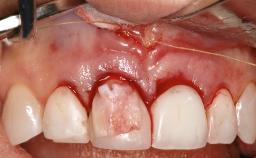

In this case, Mario Roccuzzo utilizes surgical bone regeneration treatment around implant 46 using a bone graft substitute and a connective tissue graft to resolve peri-implant inflammation, reduce the probing depths, and prevent further progression of disease.

A 58-year-old-male patient was referred in February 2007 for implant placement in the right mandibular molar area. Two tissue level implants were inserted at sites 44 and 46, respectively, to support a three-unit fixed dental prosthesis (FDP).